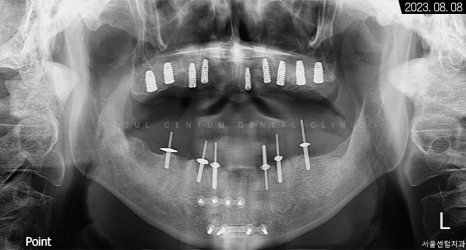

파노라마 엑스레이 사진을 보면 뿌리 주변이 골 소실로 인해 까맣다는 것을 확인할 수 있습니다.

그렇게 약 9개월의 전체임플란트 기간을 들여서 완성된 모습을 만날 수 있었는데요. 골융합을 높이기 위해 네오 브랜드와 폰틱을 결합하여 사용했습니다.

3개월이 더 지난 후 치근단 사진과 파노라마 엑스레이 사진으로 살펴봐도 초기 임플란트 식립 상황과 동일하게 견고히 자리 잡아 있는 것을 볼 수 있었습니다. 주위염도 생기지 않아 이상적인 결과를 만들어볼 수 있었어요.